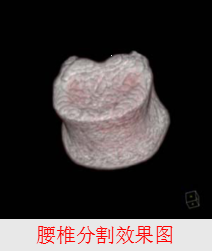

2、分割

根据目标物体特征,把图像划分为若干个互不相交的区域,使得这些特征在同一区域内,表现为一致性或相似性,在不同区域表现明显不同。

可辅助医生进行诊断和制定对病人的治疗方案;

用于医学图像的分析,如三维重建;

用于计算机引导于术,如外科手术的制定,病理的研究;

有利于数据的压缩和传输,提高在PACS和远程传输的应用。

骨密度测量

-

骨质疏松症

------骨密度降低所引发的主要病症

------高骨折风险

-

股骨近端和腰椎发生骨折的危险最高

-

欧盟: 每年约400,000例

------与年龄相关(骨折易发年龄:

女40%, 男13%, >50 岁)

骨密度测量(方法)

-

X射线摄片

-

光子吸收法

-

双能X射线吸收法

-

超声测量法

-

定量CT(Quantitative Computed Tomography, QCT)

QCT测量骨密度

对平片的手动测量

BMD = a × CTValue + b

对三维重建序列的测量

-----测量部位的分割

-----皮质骨与松质骨的分离

-----数值的测量